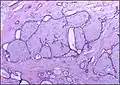

Fibroadenoma of the breast is a benign tumor composed of a biplastic proliferation of both stromal and epithelial components.[12][13] This biplasia can be arranged in two growth patterns: pericanalicular (stromal proliferation around epithelial structures) and intracanalicular (stromal proliferation compressing the epithelial structures into slit-like spaces).

These tumors characteristically display hypovascular stroma compared to malignant neoplasms.[2][14][9] Furthermore, the epithelial proliferation appears in a single terminal ductal unit and describes duct-like spaces surrounded by a fibroblastic stroma. The basement membrane is intact.[15]